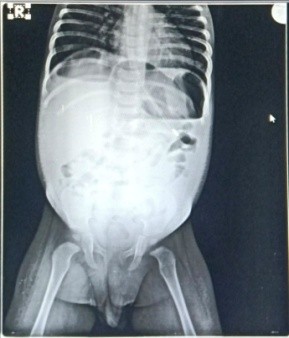

A previously healthy 1-year-old male baby was admitted with clinical signs of severe dehydration after 3 days of diarrhea, vomiting and fever. Upon admission he was lethargic and had clinical signs of shock with cold extremities, a prolonged capillary refill time (>3s) and tachycardia and abdominal distention. He was managed conservatively and advised X ray abdomen supine [Figure 1] which showed post diarrhoeal paralytic ileus with dilated bowel loops. Ultrasonography showed only mild fluid collection with internal septations. A plain abdominal x ray (erect) revealed free sub-diaphragmatic air [figure 2]. Suspecting intestinal perforation we decided to perform an exploratory laparotomy which revealed a small post-pyloric duodenal perforation [Figure 4]. Grahams patch repair was performed [Figure 5]. The postoperative course was uneventful [Figure 3]. Rotavirus antigen was found in feces.

Figure 1 X Ray Abdomen Supine Done On Day Of Admission 1 Showing Dilated Bowel Loops

Figure 1